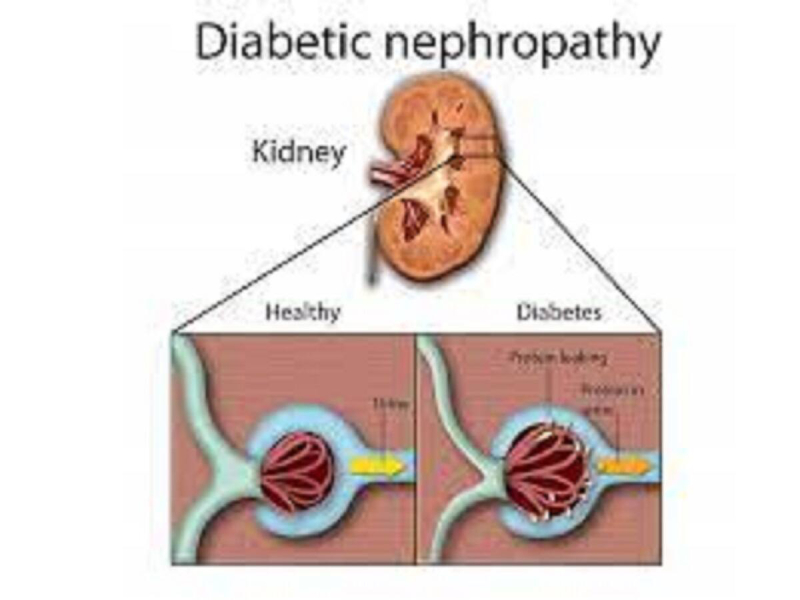

Kidney disease is also known as renal disease and nephropathy. It means damage to or disease in the kidneys. It may lead to loss of kidney function and kidney failure which is the end-stage of kidney disease. In severe cases, dialysis or a kidney transplant